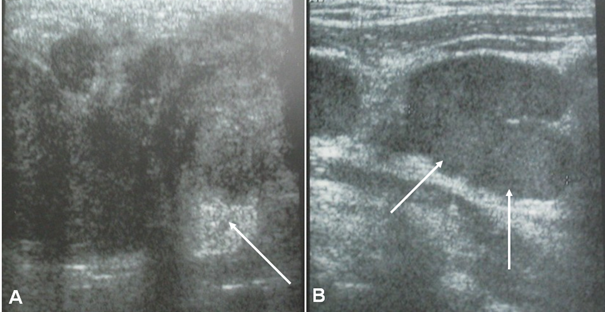

Parotid ultrasound showed an enlarged parotid with a heterogeneous tumor, poorly defined, and hyper vascularized on Doppler, associated with multiple satellite adenopathies (Figure 1). Computed tomography (CT) scan showed a parotid swollen by a parenchymal tumor, hypodense, heterogeneous, and enhancing heterogeneously after injection of contrast product. This tumor infiltrated the peri-parotid fat with multiple adenopathies of secondary appearance (Figure 2 & 3).

Figure 2 Axial CT scans of the parotid gland, without contrast: Parenchymal, hypodense, and heterogeneous tumor of the left parotid gland with multiple adenopathies.

Figure 3 Axial CT scans of the parotid gland, with contrast: parenchymal parotid gland tumor enhancing heterogeneously after injection of contrast product.